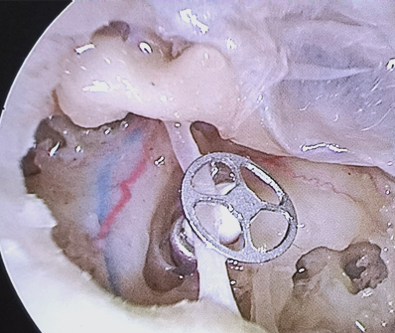

更换后人工镫骨对比图术后,老李无闭眼受限,口角歪斜等周围性面瘫